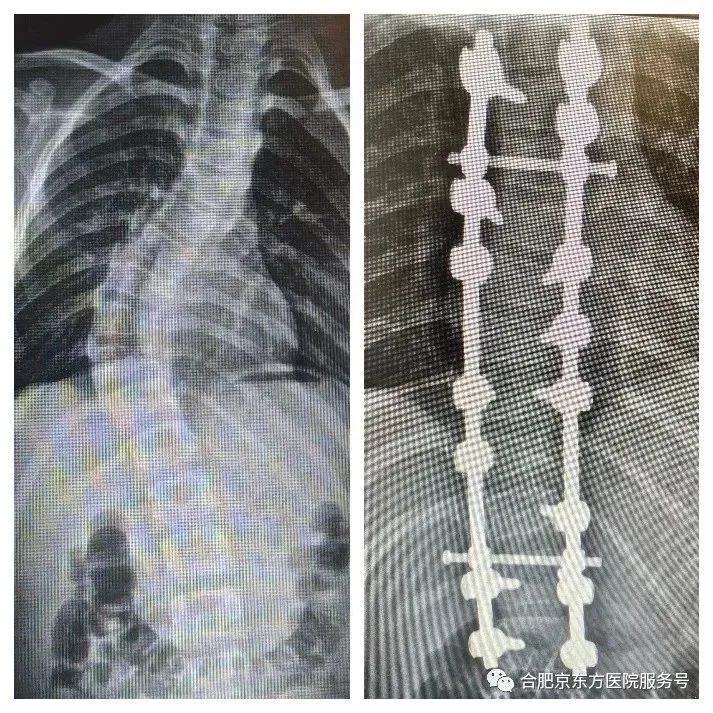

积年累月的不良姿态,让孩子脊柱侧弯程度不断加重。10 岁的涛涛脊柱侧弯角度已达到 55°,家人不忍让儿子再受此苦楚,来到我院寻求进一步救治。

2 月 12 日,手术开始,术中按照既定的手术计划一步一步实施,在脊柱畸形最为严重的地方截骨,在关键的椎体上植入 15 枚钛合金螺钉,对涛涛严重侧弯的脊柱进行彻底手术矫形。

▲术前(左)、术后(右)